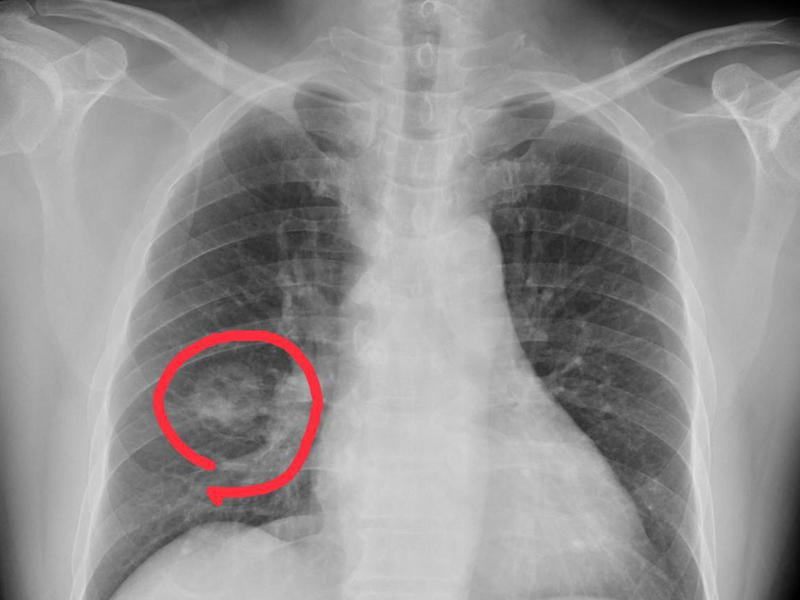

瀏覽:17181 手腳出現 4 種異常,可能是得肺癌了,千萬不要大意 | 瀏覽:2083 隔夜飯菜西瓜能吃嗎?隔夜茶能喝嗎? | 瀏覽:4502 乳房大的女性,更易患乳腺癌? |